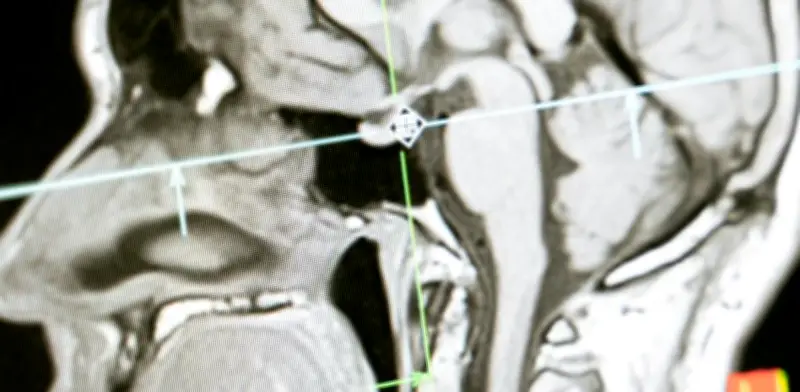

El infarto cerebral, también conocido como ictus, ocurre cuando un coágulo bloquea una arteria en el cerebro, impidiendo el flujo sanguíneo hacia zonas críticas. Esto provoca la pérdida de funciones como el habla o el movimiento. "La arteria se tapa, deja de llevar la sangre a una zona y el paciente pierde la función de esa parte del cerebro", explicó la médico internista y neuróloga Vanessa Cano durante una conferencia organizada por Boehringer Ingelheim.

Los trombolíticos, como la tenecteplasa, actúan directamente sobre el coágulo que bloquea la arteria. Su función es desintegrarlo para permitir que la sangre vuelva a fluir. "El medicamento va directamente al coágulo, rompe sus uniones y permite que la sangre vuelva a pasar", detalló Cano. Este proceso puede ayudar a recuperar funciones neurológicas si se aplica dentro de una ventana de tiempo segura, generalmente dentro de las primeras 4.5 horas tras el inicio de los síntomas.

- Estudios de imagen que descarten hemorragia.